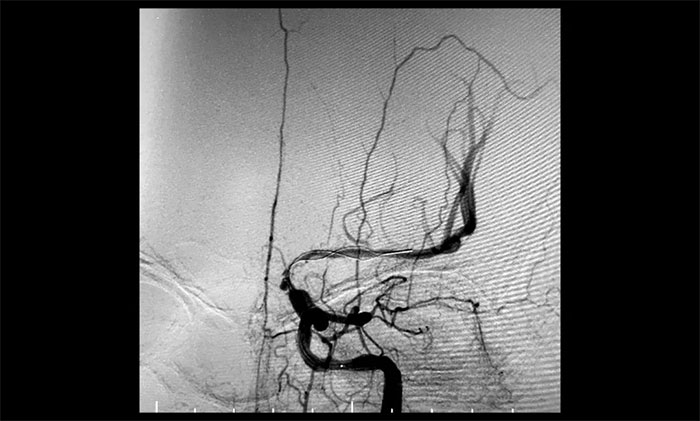

術后一個月,經(jīng)過綜合治療,患者病情穩(wěn)定。10月11日,再次行經(jīng)皮左側頸動脈慢性閉塞開通術,腦保護傘下左側頸動脈支架置入手術,經(jīng)皮左側頸動脈球囊擴張成形術。術中造影顯示,左頸內(nèi)動脈起始段多發(fā)重度狹窄,左頸內(nèi)動脈前向血流慢,左頸內(nèi)動脈巖骨段中度狹窄,左頸內(nèi)動脈眼動脈段、后交通段多發(fā)重度狹窄伴次全閉塞。

對于長節(jié)段頸動脈慢性閉塞再通,血栓逃逸是一個很重要的問題。由于患者左側頸內(nèi)動脈多處串聯(lián)病變,閉塞段血栓負荷量大,保護傘無合適著陸位置,手術風險極大,難度極高。

術中,席剛明教授、王貴平博士采用COSIS技術,在保護傘無法到位的情況下,利用Syphonet®取栓支架作為顱內(nèi)的遠端保護裝置,減少栓子逃逸,同時利用Syphonet®取栓支架的輸送導絲完成微導管交換、球囊擴張、支架置入等操作,減少器械交換,降低并發(fā)癥的發(fā)生。

經(jīng)微導絲成功進入狹窄、閉塞頸內(nèi)動脈,在支架保護下,進行球囊逐段擴張,支架置入……,經(jīng)多次球囊擴張,置入支架后,造影顯示左頸內(nèi)動脈起始段狹窄明顯改善,左頸內(nèi)動脈顱內(nèi)段順利再通,左頸內(nèi)動脈眼動脈段、后交通段狹窄明顯改善。造影及3D造影見左頸總動脈、左頸內(nèi)動脈、左大腦中動脈顯影可,行支架CT見顱內(nèi)支架成形可,手術取得成功!